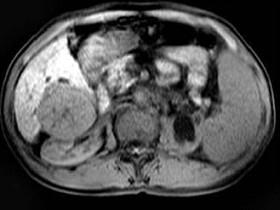

问题 男,65岁。右上腹部疼痛不适,乏力4月余。AFP升高。MRI如下图所示。应诊断为 ( )

选项 A、转移瘤 B、未见异常 C、胆管细胞癌 D、肝腺瘤 E、肝右叶肝细胞癌并门脉癌栓形成

答案 E